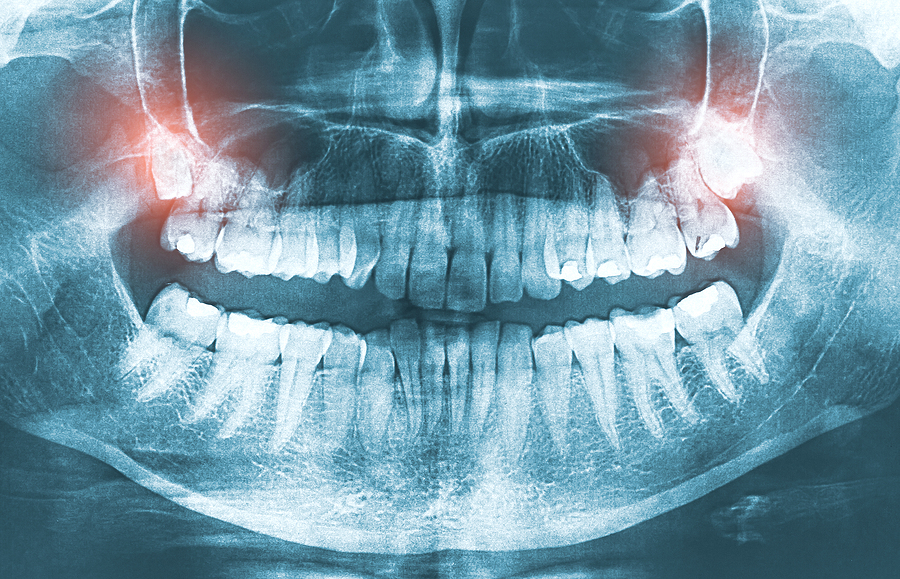

4. 歯の黄ばみや歯並び

口元の美しさには歯も大きく関係しています。黄ばんだり、歯並びが悪いと、それだけで老けた印象を与えることがあります。

原因

- 食事や飲み物によるステイン(茶渋やコーヒーの着色)

- 歯の磨き残しや加齢によるエナメル質の摩耗

対策

- ホワイトニング: 歯科医院での施術や自宅用ホワイトニングキットを活用する。

- デンタルケア: 正しい歯磨き方法を身につけ、歯石除去を定期的に行う。

- 歯列矯正: 歯並びの改善は顔全体のバランスを整える効果がある。